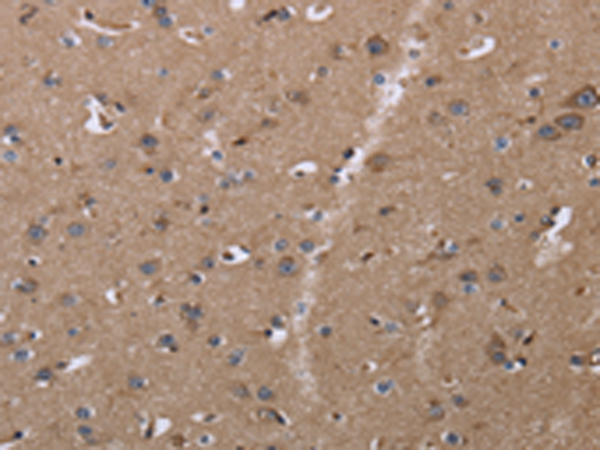

分类: 科研抗体货号: P00283别名:应用: WB,IHC反应种属: Human, Mouse, Rat